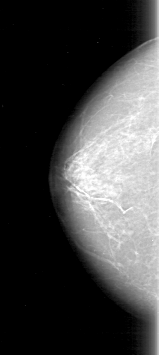

D_4097_1.LEFT_MLO

RIGHT_CC LINES 4606 PIXELS_PER_LINE 2056 BITS_PER_PIXEL 12 RESOLUTION 43.5 NON_OVERLAY